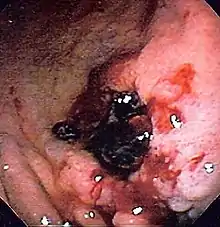

Endoscopic still of esophageal ulcers seen after banding of esophageal varices, at time of esophagogastroduodenoscopy